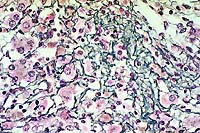

10x

obj

- Case14-4. Heart. There are multiple coalescing foci

of myocardial cell degeneration, necrosis, edema, and an inflammatory

cell infiltrate.

40x

- Case14-4. Heart. This focus of necrosis has loss of

cross striations, hyalinization, and fragmentation of cardiomyocytes,

edema, with karyorrhectic nuclei and scattered macrophages. There

are two clusters of 2-3u diameter protozoa.